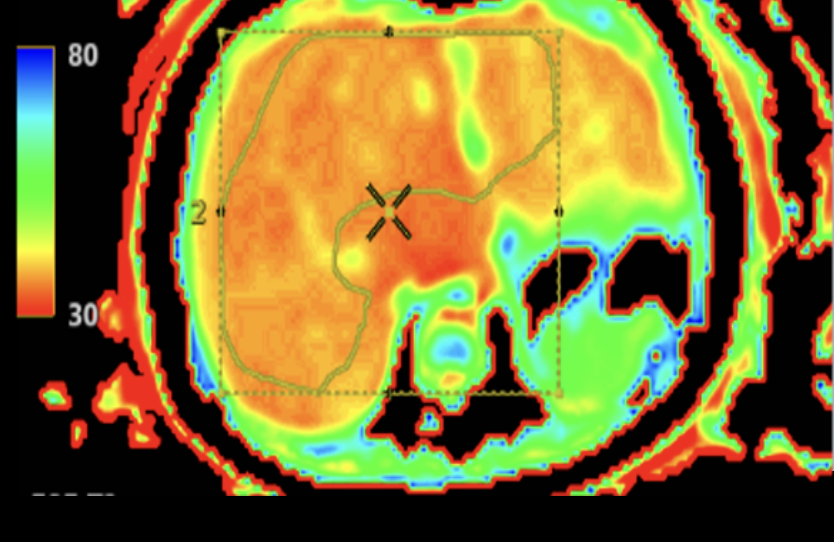

Det är en stor studie där barnen genomgår flera olika undersökningar under tre dagar. Det handlar bland annat om arbetsprov med gasanalys, hjärtultraljud, lungfunktionsundersökningar, MR av hjärta och lever, samt undersökningar av lymfsystem och blodkärl.

En annan viktig observation är att MR av hjärtat verkar ge den mest tillförlitliga bilden av hjärtfunktionen vid enkammarcirkulation. Forskarna har också sett att ökad stelhet i levern hänger ihop med förändringar i lungblodflödet.